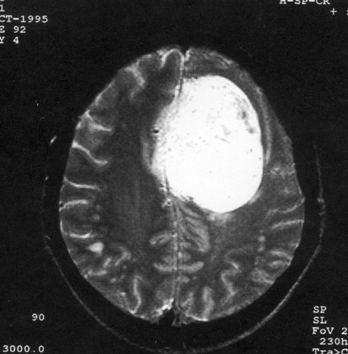

问题 病历摘要:??患者女性,37岁。大便时突起炸裂样头痛3小时,伴喷射样呕吐。既往体健。体检:T37.5℃,BP145/90mmHg,R20次/分,P85次/分。神志清楚,颅神经检查无异常,颈强直,克、布氏征(-),四肢肌力、肌张力正常,病理征(-)。 动脉瘤术中出血时,可采取哪些措施?提示:入院后第?2日患者行右翼点开颅瘤颈夹闭术,术中分离瘤颈时,动脉瘤破裂。